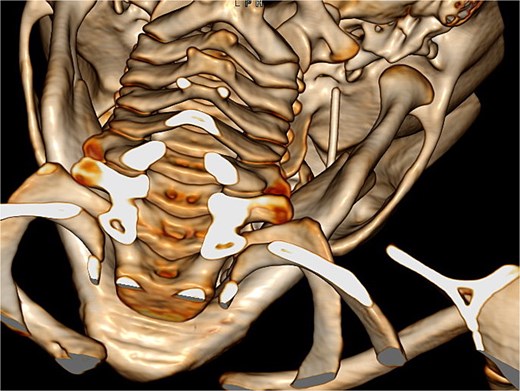

A 4-year-old girl underwent a dental filling procedure to treat a cavity in her right maxillary molar. While blocking the posterior superior alveolar nerve, the distal end of a 31-gauge injection needle broke into her pterygoid musculature. The tip of the needle was not visible, and the dentist could not retrieve it. The patient was immediately brought to the emergency department of our centre, a tertiary referral paediatric hospital. Since the nerve block was effective, the child did not experience any pain. A diagnostic CT scan revealed the needle deep in the pterygomandibular space (Fig. 1), so surgical intervention was scheduled under general anaesthesia in an operating theatre equipped with a low-radiation C-arm cone beam computed tomography (CBCT).

Diagnostic 3D CT showing the needle in the right pterygomandibular space.